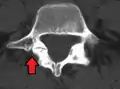

Anterolisthesis L5/S1. Blue arrow normal pars interarticularis. Red arrow is a break in pars interarticularis.